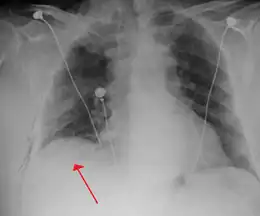

-

Anteroposterior inspired X-ray, showing subtle left-sided pneumothorax caused by port insertion -

Lateral inspired X-ray at the same time, more clearly showing the pneumothorax posteriorly in this case -

Anteroposterior expired X-ray at the same time, more clearly showing the pneumothorax in this case

Chest tube

A chest tube (or intercostal drain) is the most definitive initial treatment of a pneumothorax. These are typically inserted in an area under the axilla (armpit) called the "safe triangle", where damage to internal organs can be avoided; this is delineated by a horizontal line at the level of the nipple and two muscles of the chest wall (latissimus dorsi and pectoralis major). Local anesthetic is applied. Two types of tubes may be used. In spontaneous pneumothorax, small-bore (smaller than 14 F, 4.7 mm diameter) tubes may be inserted by the Seldinger technique, and larger tubes do not have an advantage.[14][43] In traumatic pneumothorax, larger tubes (28 F, 9.3 mm) are used.[36]

Chest tubes are required in PSPs that have not responded to needle aspiration, in large SSPs (>50%), and in cases of tension pneumothorax. They are connected to a one-way valve system that allows air to escape, but not to re-enter, the chest. This may include a bottle with water that functions like a water seal, or a Heimlich valve. They are not normally connected to a negative pressure circuit, as this would result in rapid re-expansion of the lung and a risk of pulmonary edema ("re-expansion pulmonary edema"). The tube is left in place until no air is seen to escape from it for a period of time, and X-rays confirm re-expansion of the lung.[14][18][28]